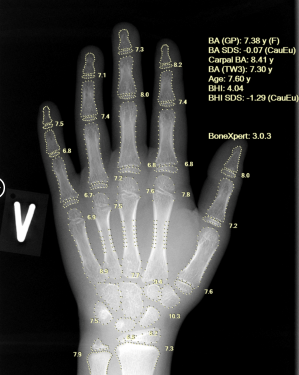

Developed by a Europe-based AI med-tech company and CE-approved, BoneXpert is widely regarded as the gold standard for automated bone age assessment. The advanced technology delivers objective, accurate and highly reproducible results, eliminating both inter- and intra-observer variability and ensuring that the same X-ray yields consistent outcomes every time.

Using a single left-hand X-ray, BoneXpert provides a multi-method, in-depth assessment, including:

- Greulich-Pyle (GP) bone age

- Tanner-Whitehouse (TW2/TW3) bone age

- Carpal bone age

- Bone Age SDS

- Bone Health Index (BHI)

This comprehensive analytical depth enables early identification of constitutional growth delay and endocrine abnormalities, while supporting long-term monitoring of skeletal growth and treatment response. Powered by advanced artificial intelligence, the system also ensures faster turnaround times without compromising clinical precision.